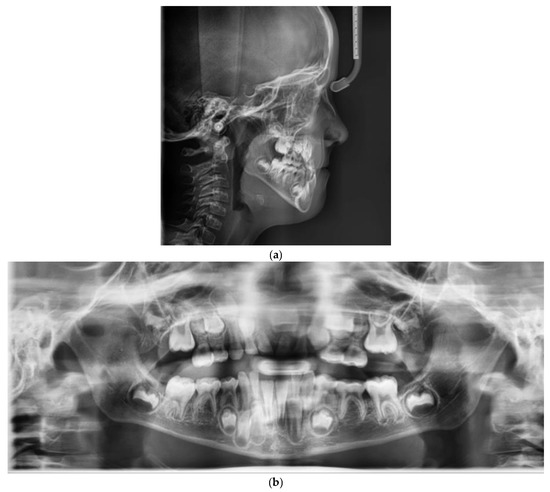

2. Case Report